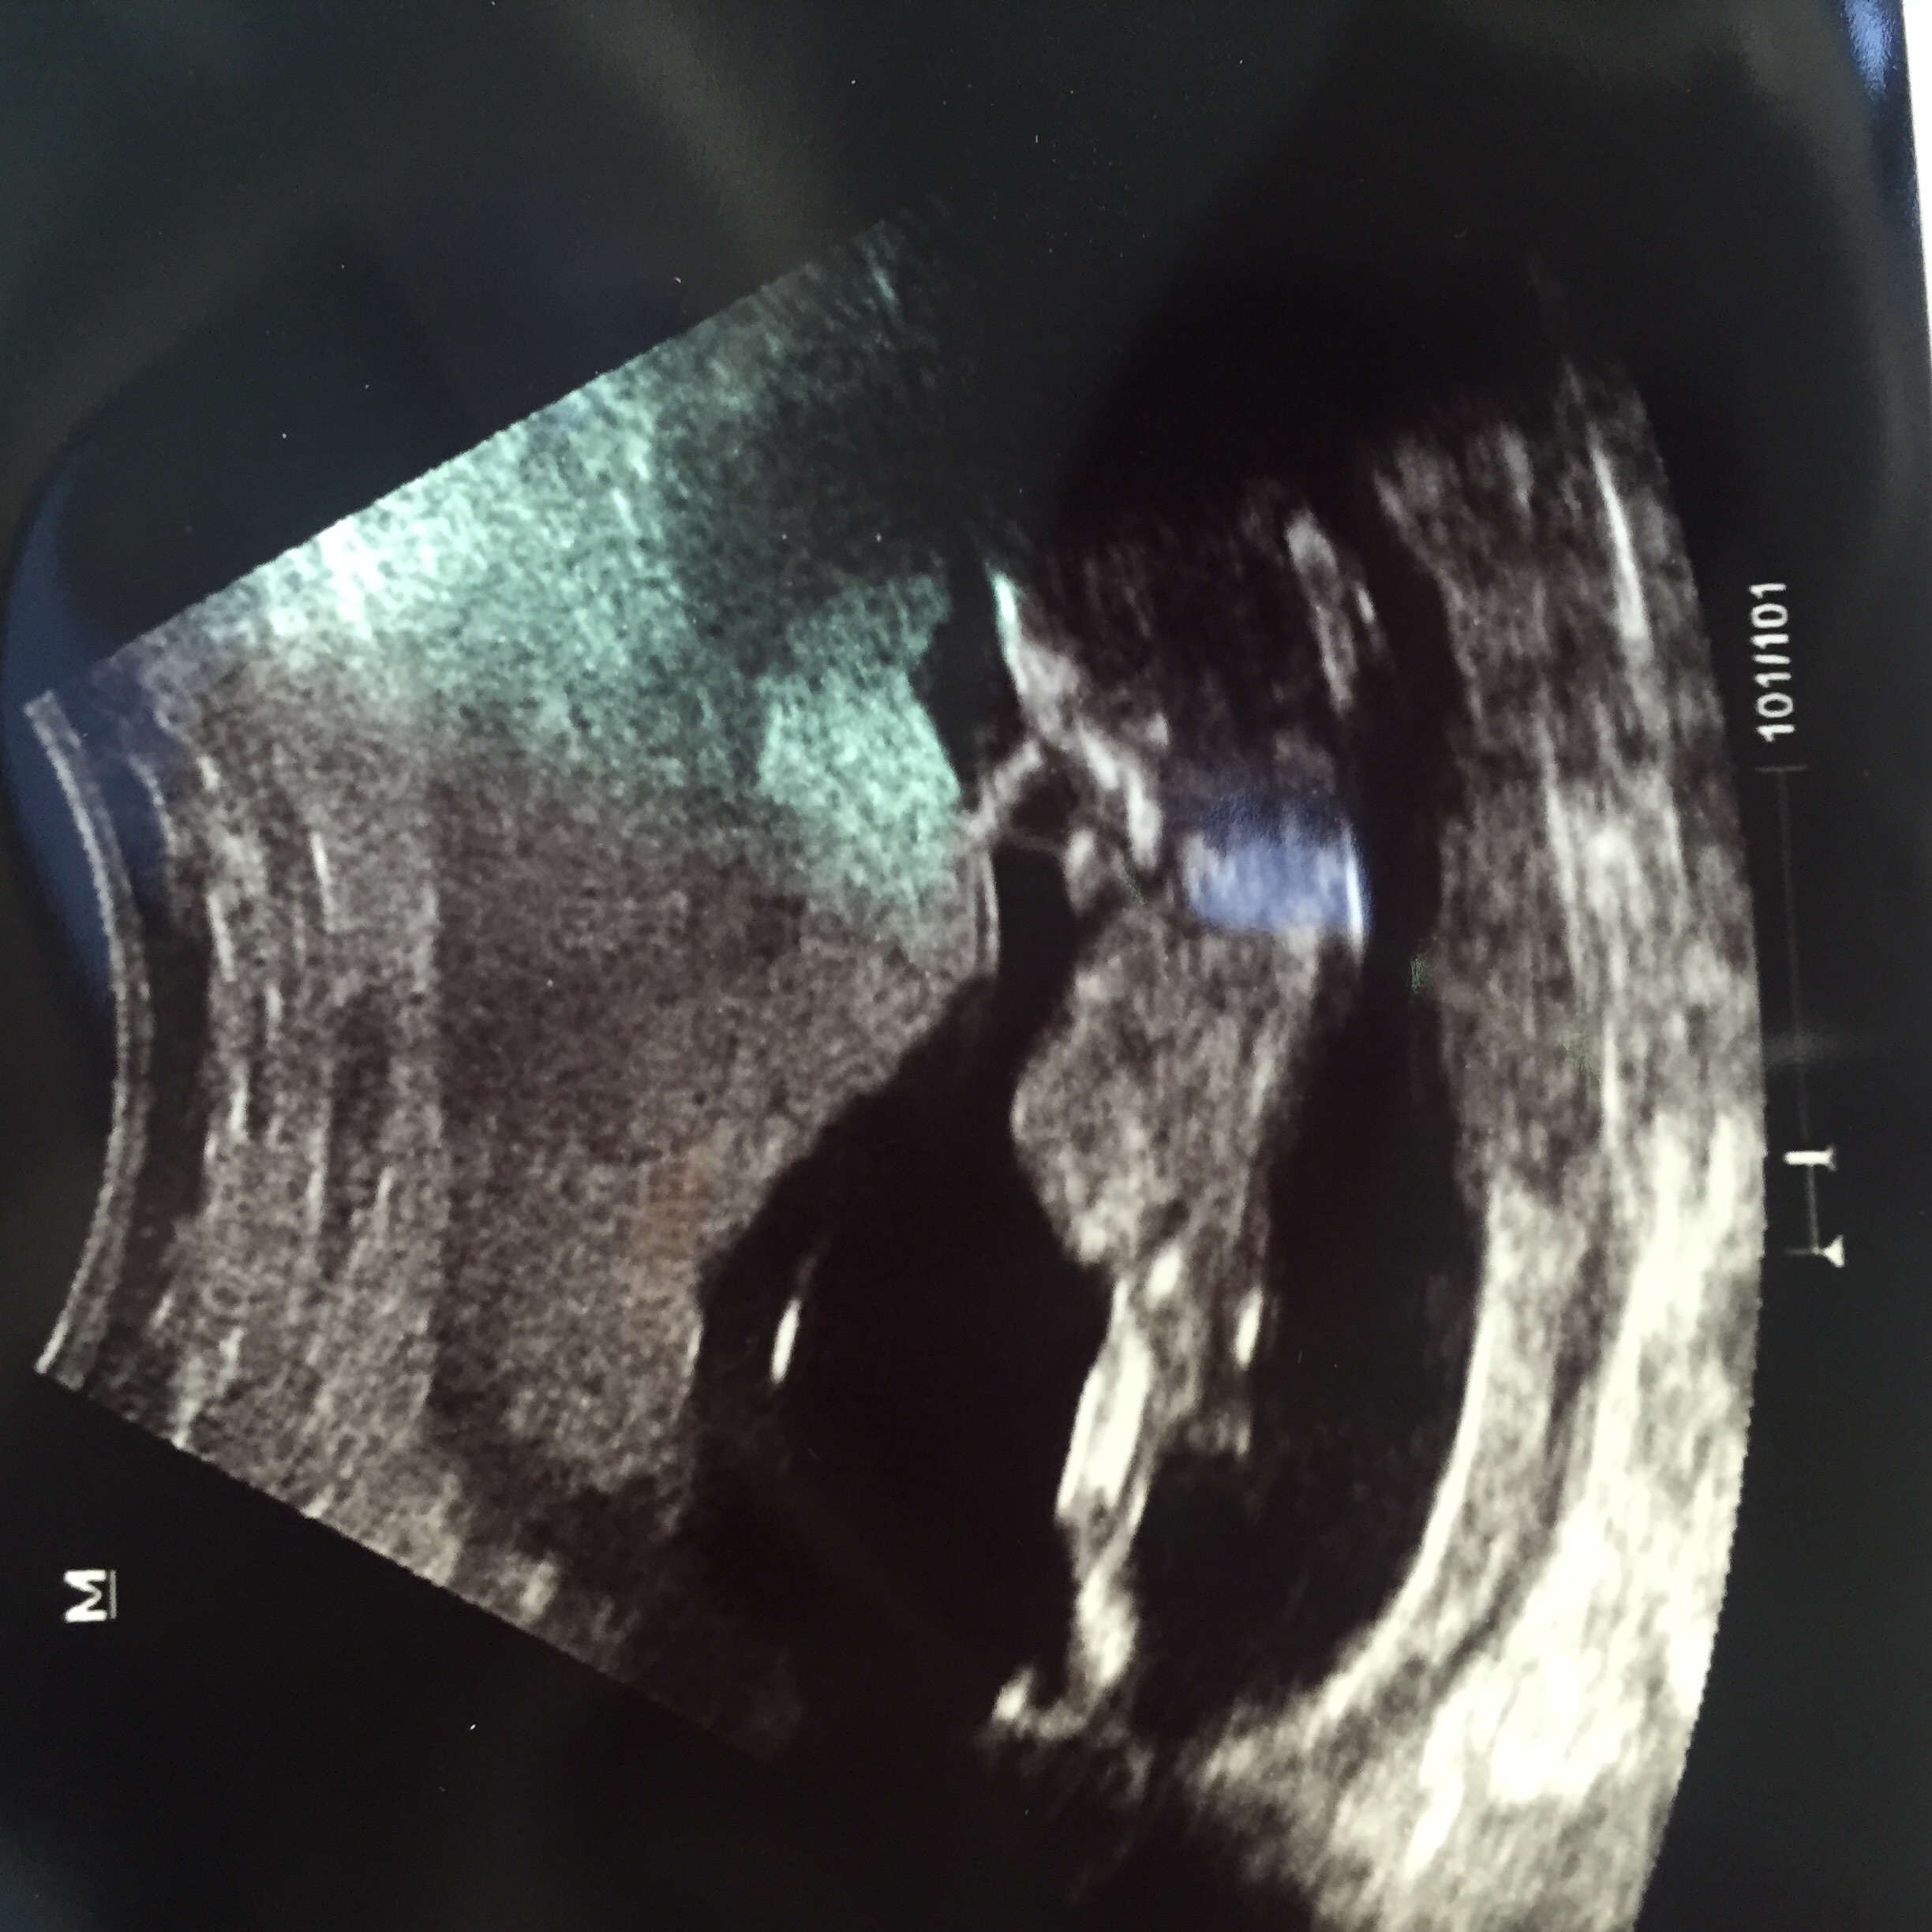

I cried and laughed so much while seeing this. My first pregnancy was a mc, and so seeing this baby wiggle and move like crazy was such a blessing! Here's my feisty little bear at 10 weeks. He/she is due to arrive May 31st.